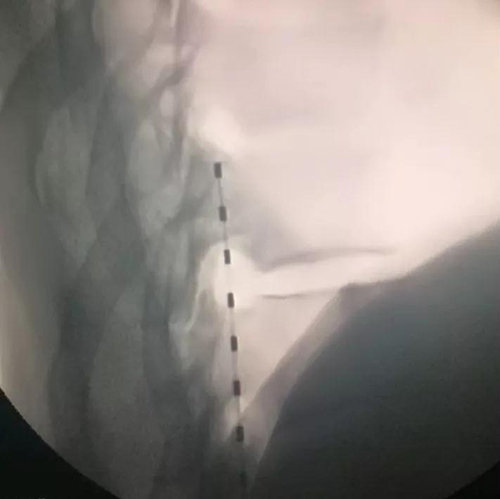

在排除了手术禁忌后,孙涛主任团队顺利完成了手术,术后当晚,张大爷露出了久违的笑脸。“我的脚不疼了”,他说:“有点麻麻的,过电的感觉,很舒服。”随后两天,张大爷下床活动,感慨终于不用跛脚走路了。如今他还在住院需要进一步的观察和电刺激参数的调整。

据悉,脊髓电刺激是一种侵入性的镇痛技术。通过植入设备发送弱电脉冲,刺激脊髓背侧特定节段,在脊髓水平,将外周感觉神经传入的痛觉以一种可以忍受的酥麻感替代,从而阻断痛觉上传到大脑中枢,达到缓解疼痛的效果。适用于脊髓电刺激的疾病有:顽固性腰腿痛或下背痛;复杂性区域疼痛综合征;带状疱疹性疼痛;难治性心绞痛;患肢/残肢痛;周围缺血性疼痛;慢性难治性心绞痛;脊髓损伤等。